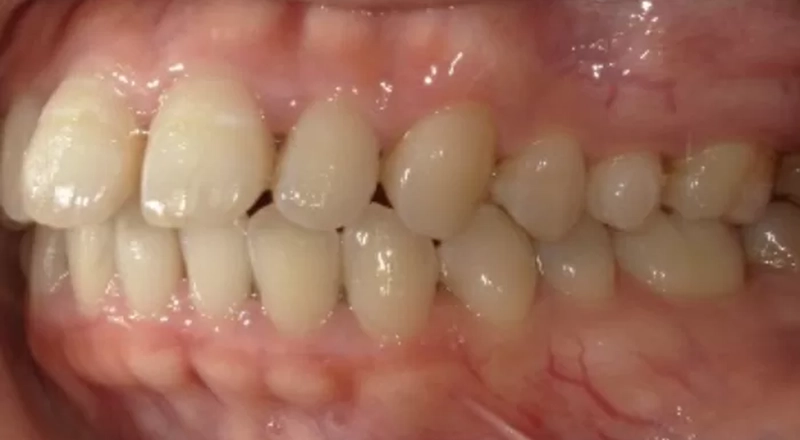

主訴

歯がでこぼこで咬みにくい

治療内容

インビザライン

治療期間

1年6ヶ月

治療費

880,000円

治療後のリスクについて

疼痛の可能性があります